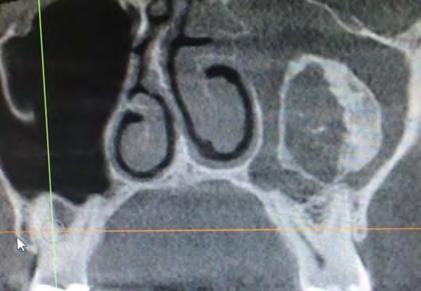

28 An Osteoma Embedding an Ectopic Wisdom Tooth within the Maxillary Sinus A Rare

Kayvan Fathimani, D.D.S., FACS, FRCD(C), FIBCSOMS

Unerupted third molar within maxillary sinus coexisting with maxillary sinus osteoma is extremely rare pathologic finding. Author describes treating patient who presented with this anomaly.

Occurrence